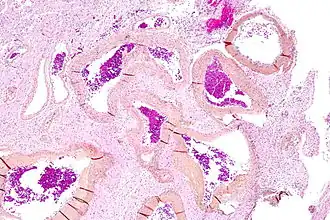

Une malformation artérioveineuse ou malformation artério-veineuse, abrégée en M.A.V, est un lien anormal entre les artères et les veines. C'est une pathologie essentiellement congénitale, mais qui peut se manifester pour la première fois assez tard dans la vie.

Les malformations artérioveineuses peuvent se trouver partout où des artères et des veines se rencontrent, perturbant le système nerveux local et les organes concernés. On peut trouver une M.A.V dans le cerveau (on l'appelle alors malformation artérioveineuse cérébrale), la rate, les poumons, les reins, la moelle épinière, le foie, les espaces intercostaux, l'iris et le cordon spermatique.